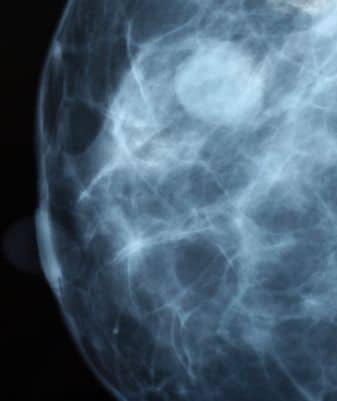

Kezdetben folyékony parafinnal próbálkoztak, de ez teljesen használhatatlannak bizonyult. Később különböző anyagok – például polietilén – beültetését kísérelték meg, de ezek az anyagok egy idő után deformálódtak és megkeményedtek. A szilikonszármazékok befecskendezésével látszatra nagyon jó eredményeket sikerült elérni, de bizonyos idő elteltével a mellben csomók képződtek, sót nemritkán amputálni is kellett később az ily módon kezelt mellet. Már abban az időben megkezdődött és még ma is szokásos a saját zsír bejuttatása. A felhasználandó zsírt a csípőről vagy a fartájról veszik. A hatvanas évek elején végre megtalálták a probléma legjobb megoldását: a szakemberek kiderítették, hogy a szilikont nem szabad közvetlenül befecskendezni. Megfelelő burokban viszont a kedvezőtlen reakciók minden veszélye nélkül, eredményesen ültethető a mellbe ez az anyag. A nagyon képlékeny és puha, szilárd, szövetszerű szilikonból készült kis tasakot folyékony szilikonnal vagy szilasztik géllel töltik meg. Ezt felfedezője után Cronin-protézisnek nevezik. Ezt a protézist mind a mai napig használjuk, és nagyon jól bevált.A gélimplantátumok különböző méretben kerülnek forgalomba, 75-től 450 köbcentiméterig. Leggyakrabban a 150-300 köbcentiméteres protéziseket használjuk. A beültetésre kerülő protézisek alakja is el térő: gömbölyú, félgömb alakú és lapos implantátumok állnak rendelkezésünkre.Újabban a tasak felszínét barázdásra képezik ki, mert ez gátolja a tokfibrosis kialakulását. Olyan implantátumokat is szoktak alkalmazni, amelyek nem géllel, hanem konyhasóoldattal vannak töltve. Ezek beültetésekor először csak az üres burkot vezetik be, és egy szelepen át töltik meg a sóoldattal. Ennek a módszernek kétségtelen előnye az, hogy a metszés valamivel kisebb lehet, és hogy a betöltendő folyadék mennyiségét egészen pontosan meg lehet határozni. Hátránya azonban, hogy a szelep néha ereszteni szokott. Végül arról is említést kell tenni, hogy léteznek kettős üregrendszerű implantátumok is. Ezek tulajdonképpen az előzőleg ismertetett protézisek kombinációi: a belső zsák szilasztik gélt tartalmaz, és ezt egy olyan üreg veszi körül, amelyet konyhasóoldattal lehet feltölteni. Mindhárom implantátumtípusról el lehet mondani, hogy nemcsak a kívánt nagyságúvá és alakúvá teszik a mellet, hanem rugalmas, lágy jellegük miatt a beültetés után tapintással sem lehet jelenlétükre következtetni.